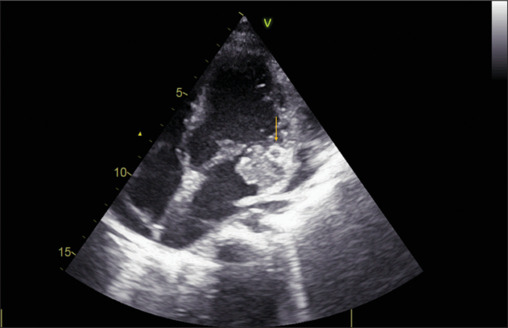

Figure 1.

Transthoracic echocardiographic apical 4-chamber view showing hypoechoic shadow adjacent to posterior mitral valve leaflet (arrow)

On examination, the patient was febrile, pulse rate was 134/min, respiratory rate was 33/min, oxygen saturation was 99% on room air, and blood pressure was 90/60 mm Hg. Her left knee had mild swelling. On auscultation, a holosystolic murmur of mitral regurgitation and bilateral basal crepitations over the lung fields were found. The chest X-ray showed cardiomegaly and mild pulmonary congestion. An electrocardiogram revealed sinus tachycardia with no chamber enlargements. The laboratory examination showed leukocytosis with a total leukocyte count of 18,260/mm3. Hemoglobin was 10.5 gm/dL. C-reactive protein was 228 mg/L. Two blood cultures grew S. maltophilia, a Gram-negative bacillus, sensitive to cotrimoxazole, levofloxacin, and minocycline but resistant to penicillin, cephalosporins, and vancomycin. The transthoracic echocardiogram demonstrated the presence of a large vegetation attached to the posterior mitral valve leaflet (PMVL), causing an eccentric jet of severe mitral regurgitation and moderate pericardial effusion. Adjacent to the PMVL, a hypoechoic shadow extending to the lateral left ventricular wall was noted, indicating a myocardial abscess [Figure 1 and Supplementary Video 1]. Cardiac computed tomography (CT) done subsequently also showed the evidence of an abscess as a hypodense area with peripheral enhancement below PMVL [Figure 2]. Additionally, a pseudoaneurysm arising superior to the mitral valve below the left atrial appendage was identified [Figure 3]. Evidence of septic pulmonary emboli was identified on the CT lung images.